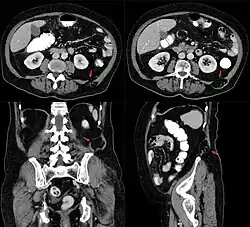

Grynfeltt-Hernie links in der Computertomographie.

Petit-Hernie links in der Computertomographie.

Bei lumbalen, also im Lendenbereich auftretenden Hernien erfolgt der Durchtritt von Fett oder anderen abdominellen Strukturen nach hinten außen entweder oben unterhalb der 12. Rippe durch das Trigonum lumbale superius (Grynfeltt-Hernie) oder unten oberhalb des Beckenkamms durch das Trigonum lumbale inferius (Petit-Hernie).